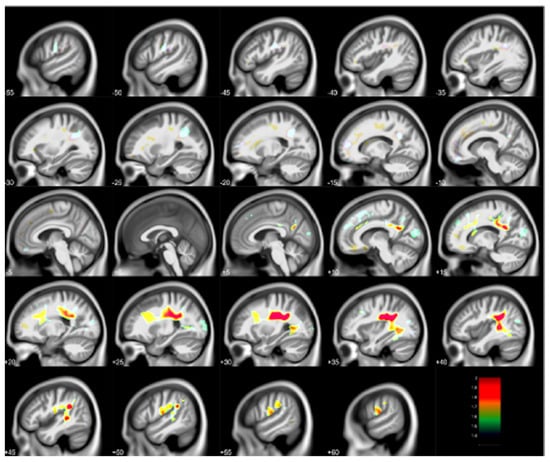

- Rauh, V.A.; Perera, F.P.; Horton, M.K.; Whyatt, R.M.; Bansal, R.; Hao, X.; Liu, J.; Barr, D.B.; Slotkin, T.A.; Peterson, B.S. Brain anomalies in children exposed prenatally to a common organophosphate pesticide. Proc. Natl. Acad. Sci. USA 2012, 109, 7871–7876. [Google Scholar] [CrossRef] [Green Version]

| Prenatal, Postnatal PAH | MRI | Child | 3rd Trimester PAH with reduced white matter surface | Peterson et al. [30] |